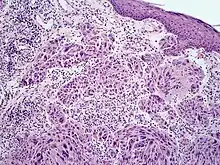

Spitzoid melanoma

Melanoma with features of a Spitz nevus (also known as a "Spitzoid melanoma") is a cutaneous condition characterized histologically with tissue similar to a spitz nevus and with overall symmetry and a dermal nodule of epithelioid melanocytes that do not mature with progressively deeper dermal extension.[1]